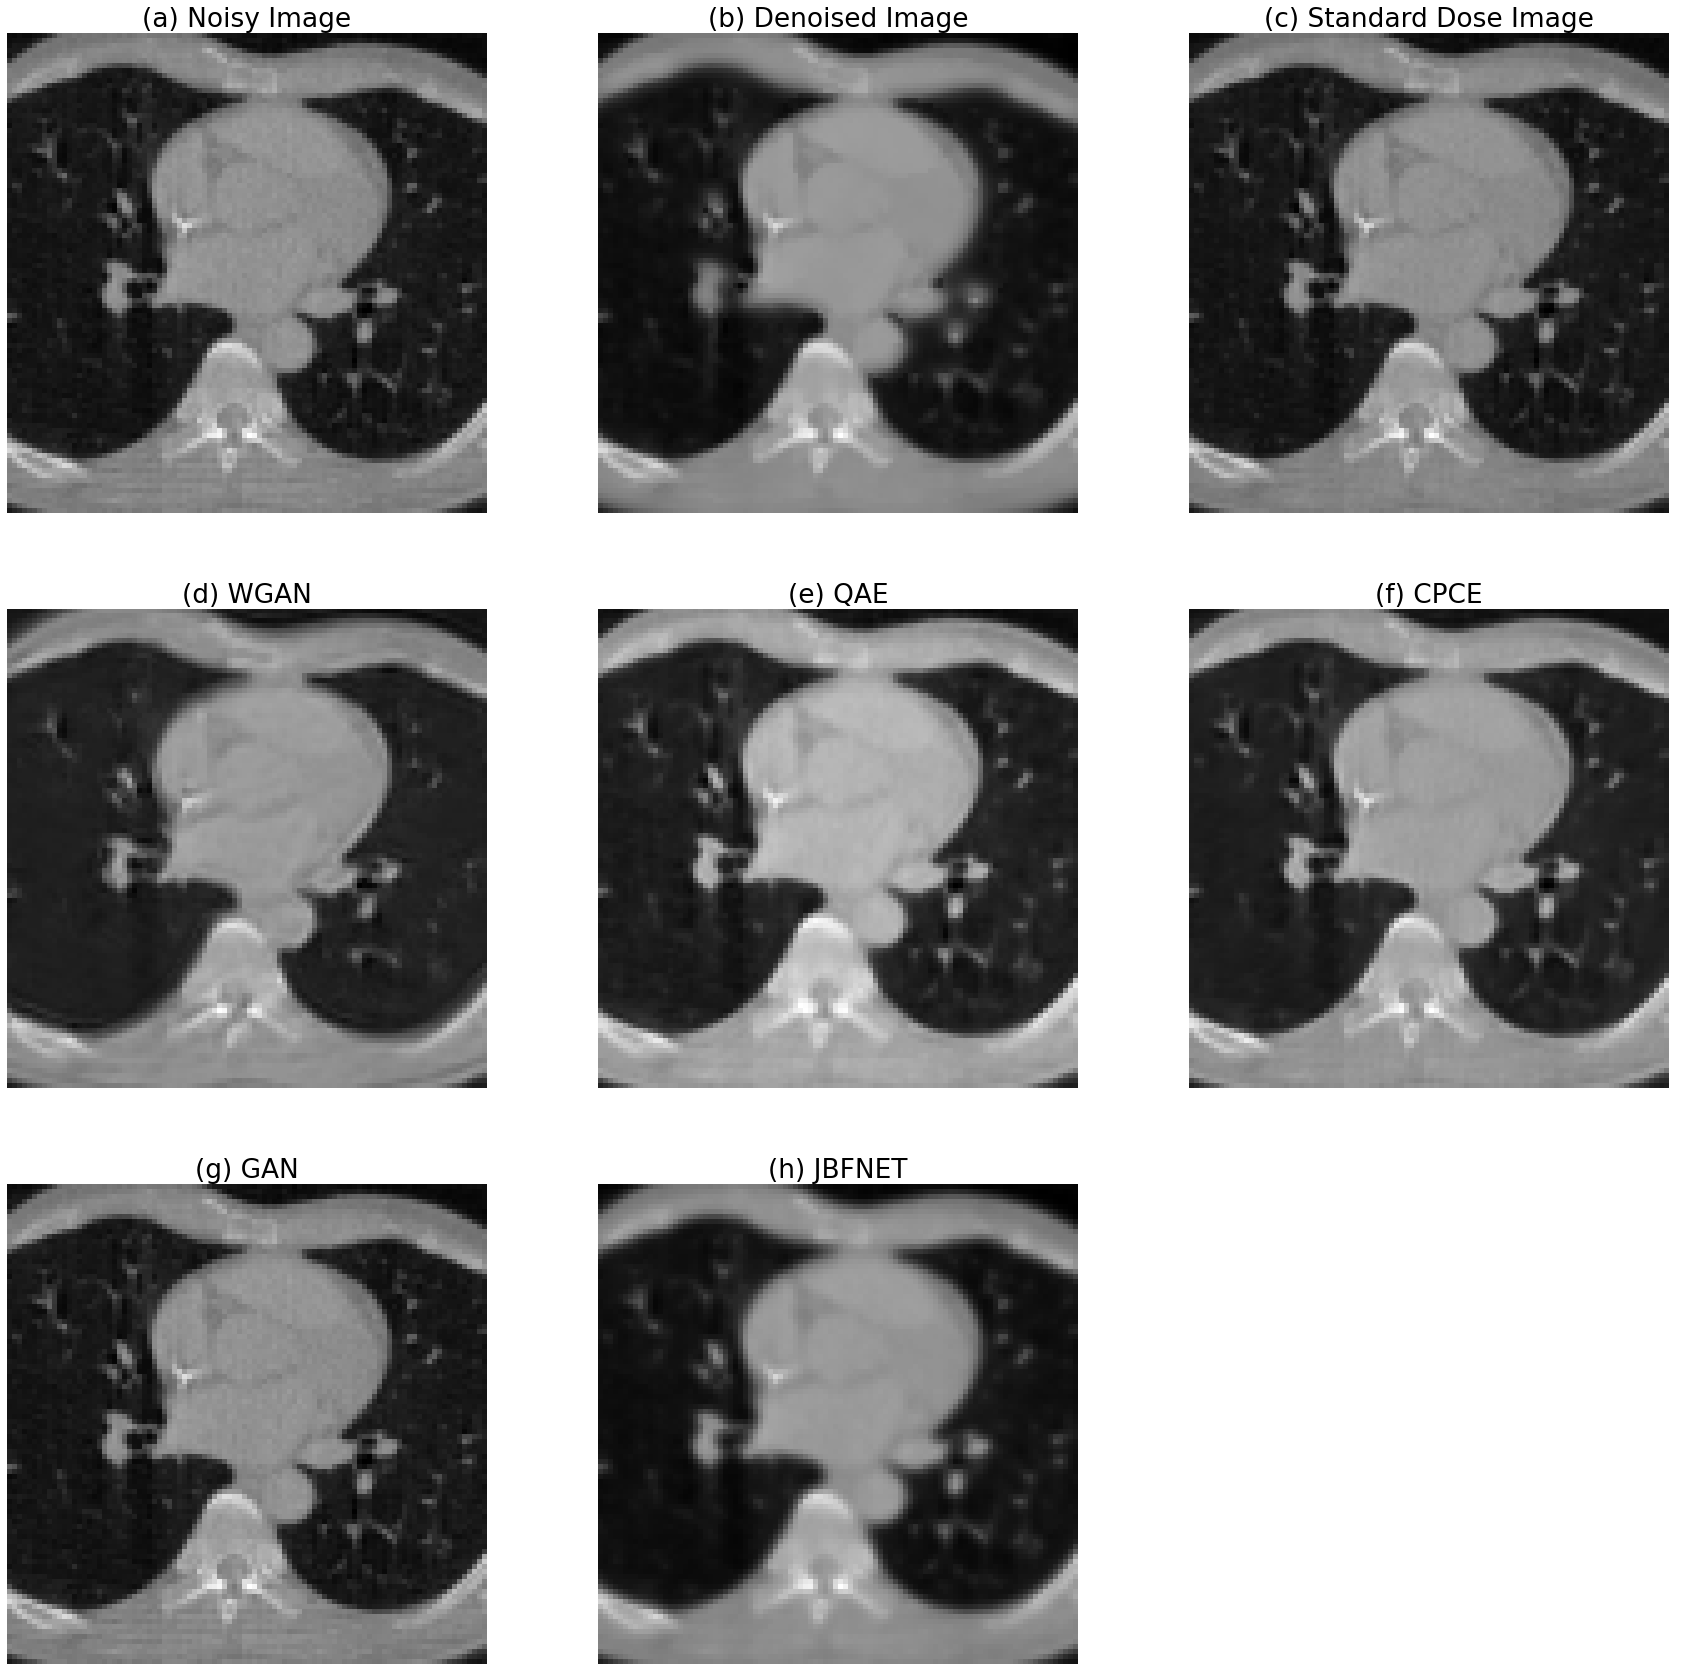

Refer to caption

Figure 4: Denoising results compared to other methods

Figure 4 shows the results from our approach and other methods pretrained with other CT images. the results can be compared to others.

We can find that JBFNet and this approach were robust to some points. It is because the others are basically based on image translation neural network models. However our approach and JBFNet learn parameters for filtering. therefore, it doesn’t get effected so much on the difference of geometries or image range, etc. Therefore, those approaches can have comparably robust results.

There is a proof for the image domain range issue in Figure 4. after matching the image domain range to how much the models are pre-trained with training dataset with. the images quality got better notably. it can be one of future benefits of using this approach. this method can be robust to any range of HUs so that it can be applied to general problems. before matching the domain, the metric values including PSNR and SSIM of the GAN-based models don’t look good, which means GAN-based models are over-sensitive to the image domain range and geometries of training data. and on the other hand, QAE, JBFNet, this approach are robust from image domain range issue.

Figure 5: Specific areas of results including results from other methods

In Figure 5, we can compare specific areas of results. There is a disadvantage of models based on domain filtering including our works and JBFNET. the image in the middle is clearer than others but the outside of images are a bit blurry.

In the results quality point of view, Table 1 shows that each PSNR and SSIM of the results compared to the standard dose. and the values are means of overall experiments. overall qualities was also interesting. it is same or similar to low dose Cone Beam Computed Tomograph(CBCT) results which means this approach can preserve features for the patients well and also the denoising quality is also good.